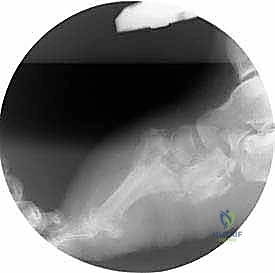

عندما تتضافر هاتان النظريتان، ينهار قوس القدم تماماً، وتبرز العظام نحو الأسفل، مما يخلق ما يُعرف بـ "قدم الكرسي الهزاز" أو "قدم الروكر" (Rocker-bottom Foot)، حيث يصبح باطن القدم محدباً بدلاً من أن يكون مقعراً. هذا البروز العظمي يضغط بشدة على الجلد من الداخل، مما يؤدي سريعاً إلى تقرحات عميقة، التهابات بكتيرية، وتسمم الدم، وهو ما ينتهي غالباً بالبتر إذا لم يتم التدخل الجراحي المتخصص في الوقت المناسب.

- المرحلة الثالثة (مرحلة التصلب وإعادة البناء): تبرد القدم وتستقر، لكنها تلتئم على وضع مشوه بشدة (قدم الروكر)، مما يمهد الطريق للتقرحات المستعصية.